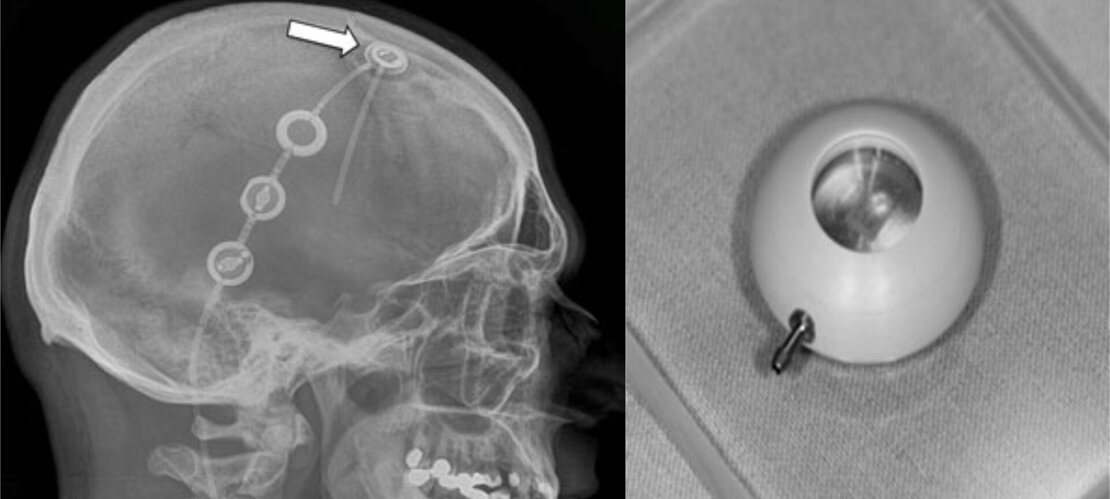

Bei dieser neuen und modernen Form der Hirndruckmessung implantieren wir den Patienten einen Drucksensor unter die Kopfhaut. Mit speziellen Empfängern können Hirndruckwerte telemetrisch durch die geschlossene Haut übertragen werden. Es existieren Drucksensoren, die als eigenständiges Implantat verwendet werden, als auch Sensoren, die in eine Hirnwasserableitung (in einen sog. Shunt, siehe unten) integriert werden. Neben diagnostischen Messungen zur Feststellung einer behandlungsbedürftigen Erkrankung können auch postoperative Überwachungen des Hirndrucks nach neurochirurgischen Operationen am Hirnwassersystem durchgeführt werden. Die Integration eines Drucksensors (Miethke Sensor Reservoir, siehe Abbildung) in einen Shunt bietet zudem die Möglichkeit, jederzeit die Funktion der Hirnwasserableitung zu überprüfen. Durch unsere jahrelange Expertise bei der Messung und Interpretation von Hirndruckwerten können wir so eine patientenindividuelle Behandlung durchführen.